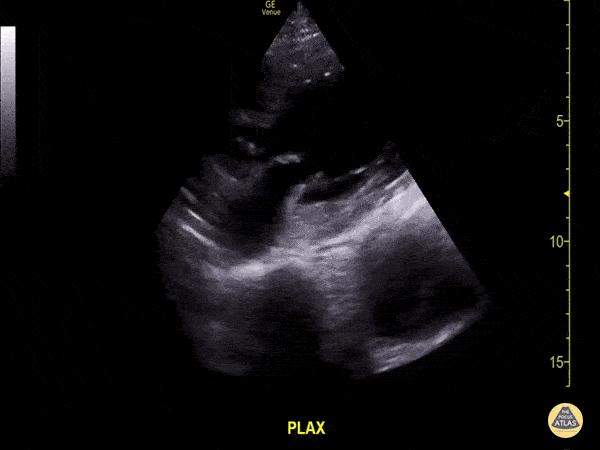

A 74-year-old with ischemic cardiomyopathy, HTN, and diabetes presents with 5 days of worsening exertional dyspnea, orthopnea, fatigue, and reduced exercise tolerance, but denies active chest pain. Vitals: T 36.7°C, HR 112, BP 94/62, RR 24, SpO₂ 92% on room air. Exam: bibasal crackles, S3, 2+ bilateral pitting edema. A parasternal long-axis clip is shown. Please describe the findings seen in this scan. What is the diagnosis?

Findings: Fractional shortening < 30%, EPSS > 1, grossly depressed LV systolic function

Diagnosis: Acute decompensated heart failure with reduced EF